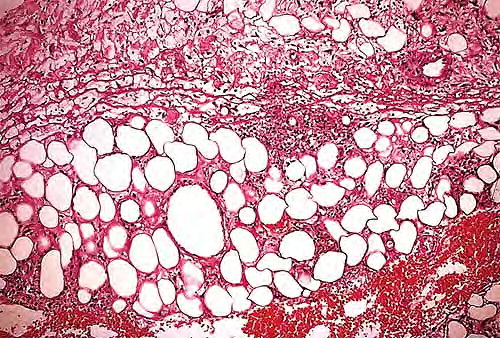

Read MoreMycobacterial panniculitis = التهاب السبلةالشحمية بالمتفطرات Infections with Nontuberculosis Mycobacteria Among the nontuberculosis, nonleprosy mycobacterial infections of the skin, those caused by M. marinum are the most common among nonimmunosuppressed people . Unlike M. tuberculosis, which is transmitted from person to person, nontuberculosis mycobacteria are abundant in nature, in soil and water, and contact is […]